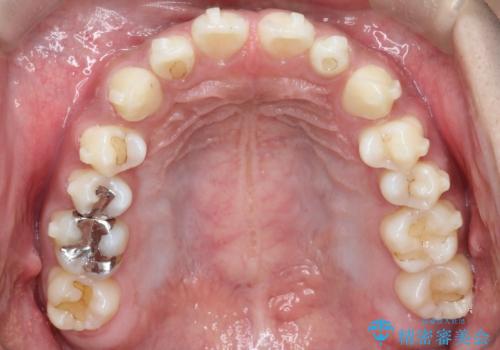

【インビザライン】空隙歯列の矯正

- 前歯の隙間を主訴に来院されました。

なるべく目立たない治療を希望されましたので、インビザラインにて治療を行なっております。

単純に前歯の隙間の閉鎖をしてしまうと、前歯に早期接触が生まれ、臼歯が噛まなくなってしまいます。適切な治療計画を立てることで、噛み合わせも良好な結果を得ることができました。